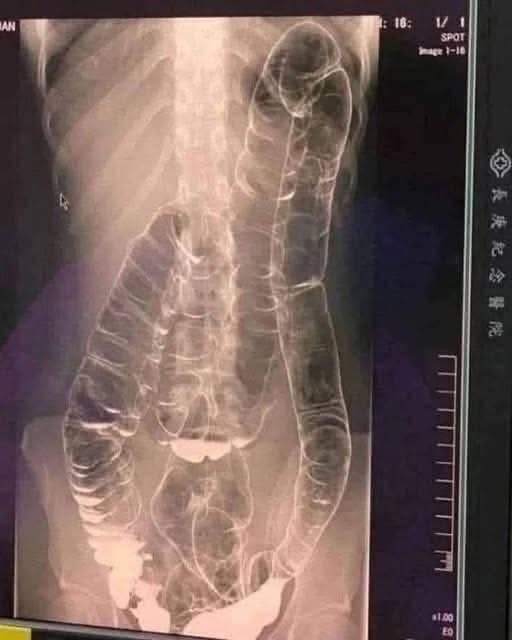

Severe Constipation and Toxic Megacolon: Causes and Solutions

Constipation Can Be Dangerous if Ignored

Chronic constipation isn’t just uncomfortable—it can lead to serious health risks like colon distension, toxin buildup, hemorrhoids, bowel obstruction, and even increased cancer risk.